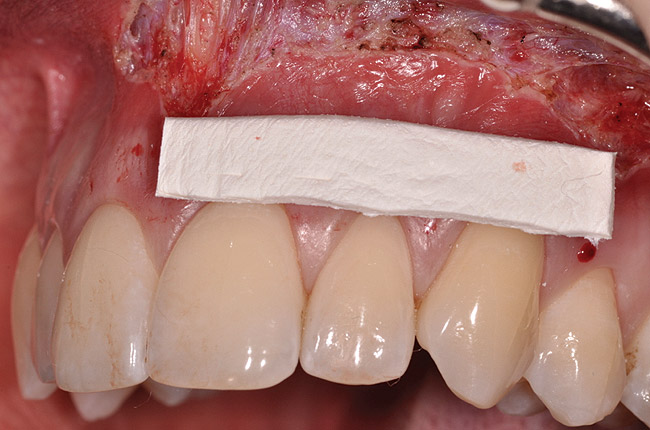

Fig 8. Dermis selected, and sized for defect.

Figure 8

After administration of an appropriate local anesthetic, a laser-assisted split-thickness vestibuloplasty was performed superior to the mucogingival junction from the right central incisor to the left first premolar region (Figure 7). Prior to any incisions being performed, a 20-mm x 40-mm dermal matrix graft (Puros Dermis), a 0.8-mm to 1.7-mm thick piece of tissue, was trimmed to appropriate length and width to correct the gingival defect present (Figure 8). The tissue graft was sized to 6 mm in height and spanned to the mesial line angle of the left central incisor to the distal line angle of the left canine area. The dermal matrix graft was rehydrated with the patient’s own platelet-rich plasma solution, which was harvested from 20 cc of whole blood collected immediately prior to the surgical procedure (Figure 9).